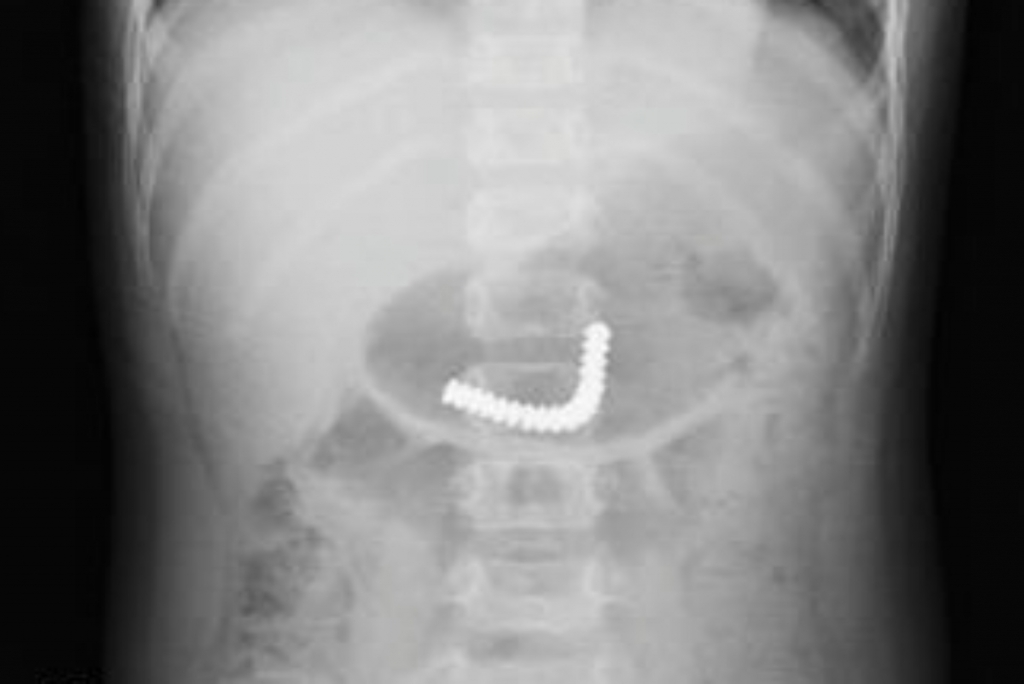

Sáu giờ trước khi vào Bệnh viện Nhi đồng Thành phố hôm 21/12, bé cầm chơi rồi nuốt các nút nam châm này. Sau đó bé không đau bụng, không ói nhưng vô cùng hoảng loạn. Lúc này, các viên nam châm kết thành chùm, trôi xuống ruột non bé, bác sĩ phải mổ nội soi khẩn cấp để lấy ra.

18 viên nam châm trong ruột non bệnh nhi. Ảnh: Phương Vũ. |